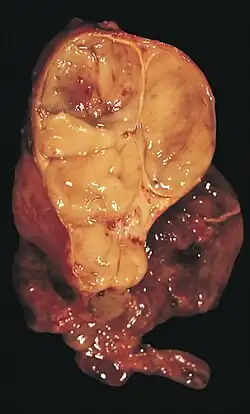

| An encapsulated thymoma (mixed lymphocytic and epithelial type) | |

Gallery

-

An encapsulated cystic thymoma. -